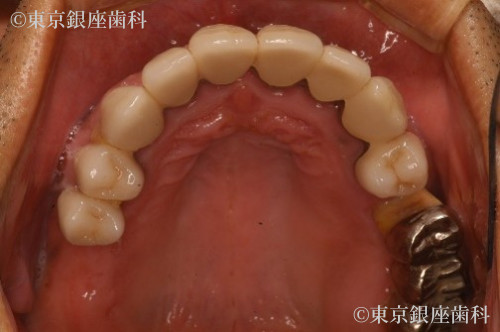

After

重度の歯周病により骨が吸収されているため、上顎骨が薄く右側は上顎洞に骨を足す治療(サイナスリフト)を行い上顎に5本、下顎に4本のインプラントを埋入しワンデイインプラントを行った。

抜歯即時埋入でインプラント治療を行い、その日のうちに仮歯を入れて短期間での大幅な審美、機能の回復をした。

また上顎骨が薄くインプラント埋入の難しい部位には人口骨を足しインプラント埋入を可能にした。